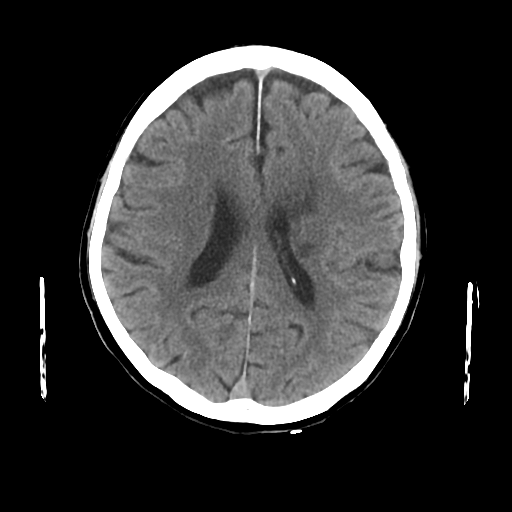

1-1. 高吸収領域の検出・表示例(下)

頭部CT検査において、周囲に比べ白く映る部分(高吸収領域)が見られる場合には、脳出血が疑われます。脳出血は高血圧・脳腫瘍・脳血管の異常などが要因となり、脳の動脈が破れて脳内部に出血した状態を指します。一方、周囲に比べ黒く映る部分(低吸収領域)が見られる場合には、脳梗塞が疑われます。脳梗塞は、脳内の血管が詰まるなどにより血液の流入が止まり、脳に酸素や栄養が行き渡らなくなる状態です。また、急性期の脳梗塞では、頭部CT検査において、灰白質と白質の境界が消失するなどの所見(ECS=early CT sign)が見られ(2)、こうした所見を見落とさずに治療につなげることが肝要です。